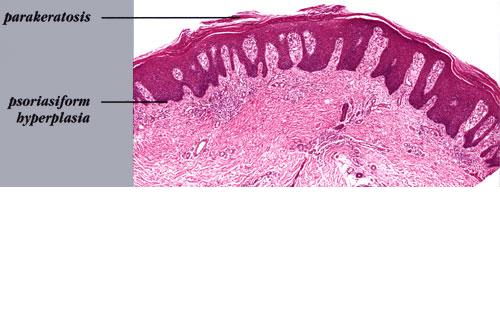

Psoriasis Vulgaris Histopathology The histologic picture of psoriasis vulgaris varies considerably with the stage of the lesion and usually is diagnostic only in early, scaling papules and near the margin of advancing plaques. |

exocytosis of neutrophils, they may aggregate in the uppermost portion of the spinous layer to form small spongiform pustules of Kogoj. Lymphocytes remain confined to the lower epidermis, which, as more and more mitoses occur, becomes increasingly hyperplastic. The epidermal changes are at first focal, but later become confluent, leading clinically to plaques. In the fully developed lesions of psoriasis, as best seen at the margin of enlarging plaques, the histologic picture is characterized by (a) acanthosis with regular elongation of the rete ridges with thickening in their lower portion; (b) thinning of the suprapapillary epidermis with the occasional presence of small spongiform pustules; (c) pallor of the upper layers of the epidermis; (d) diminished to absent granular layer; (e) confluent parakeratosis; (f) the presence of Munro microabscesses; (g) elongation and edema of the dermal papillae; and (h) dilated and tortuous capillaries . |

The rete ridges show considerable elongation and extend downward to a uniform level, resulting in regular acanthosis . They are often slender in their upper portion but |

show thickening ("clubbing") in their lower portion. Not infrequently, adjacent rete ridges seem to coalesce at their bases due to tangential sectioning. Usually, intercellular and intracellular edema is absent in the rete ridges, and keratinocytes located well above the basal layer show deep basophilia. In addition, mitoses are not limited to the basal layer as in normal skin but are also seen above the basal layer. This, together with a considerable lengthening of the basal cell layer due to elongation of the rete ridges, results in a marked increase in the number of mitoses. This increase has been calculated to be 27 times the number of mitoses in uninvolved skin . |